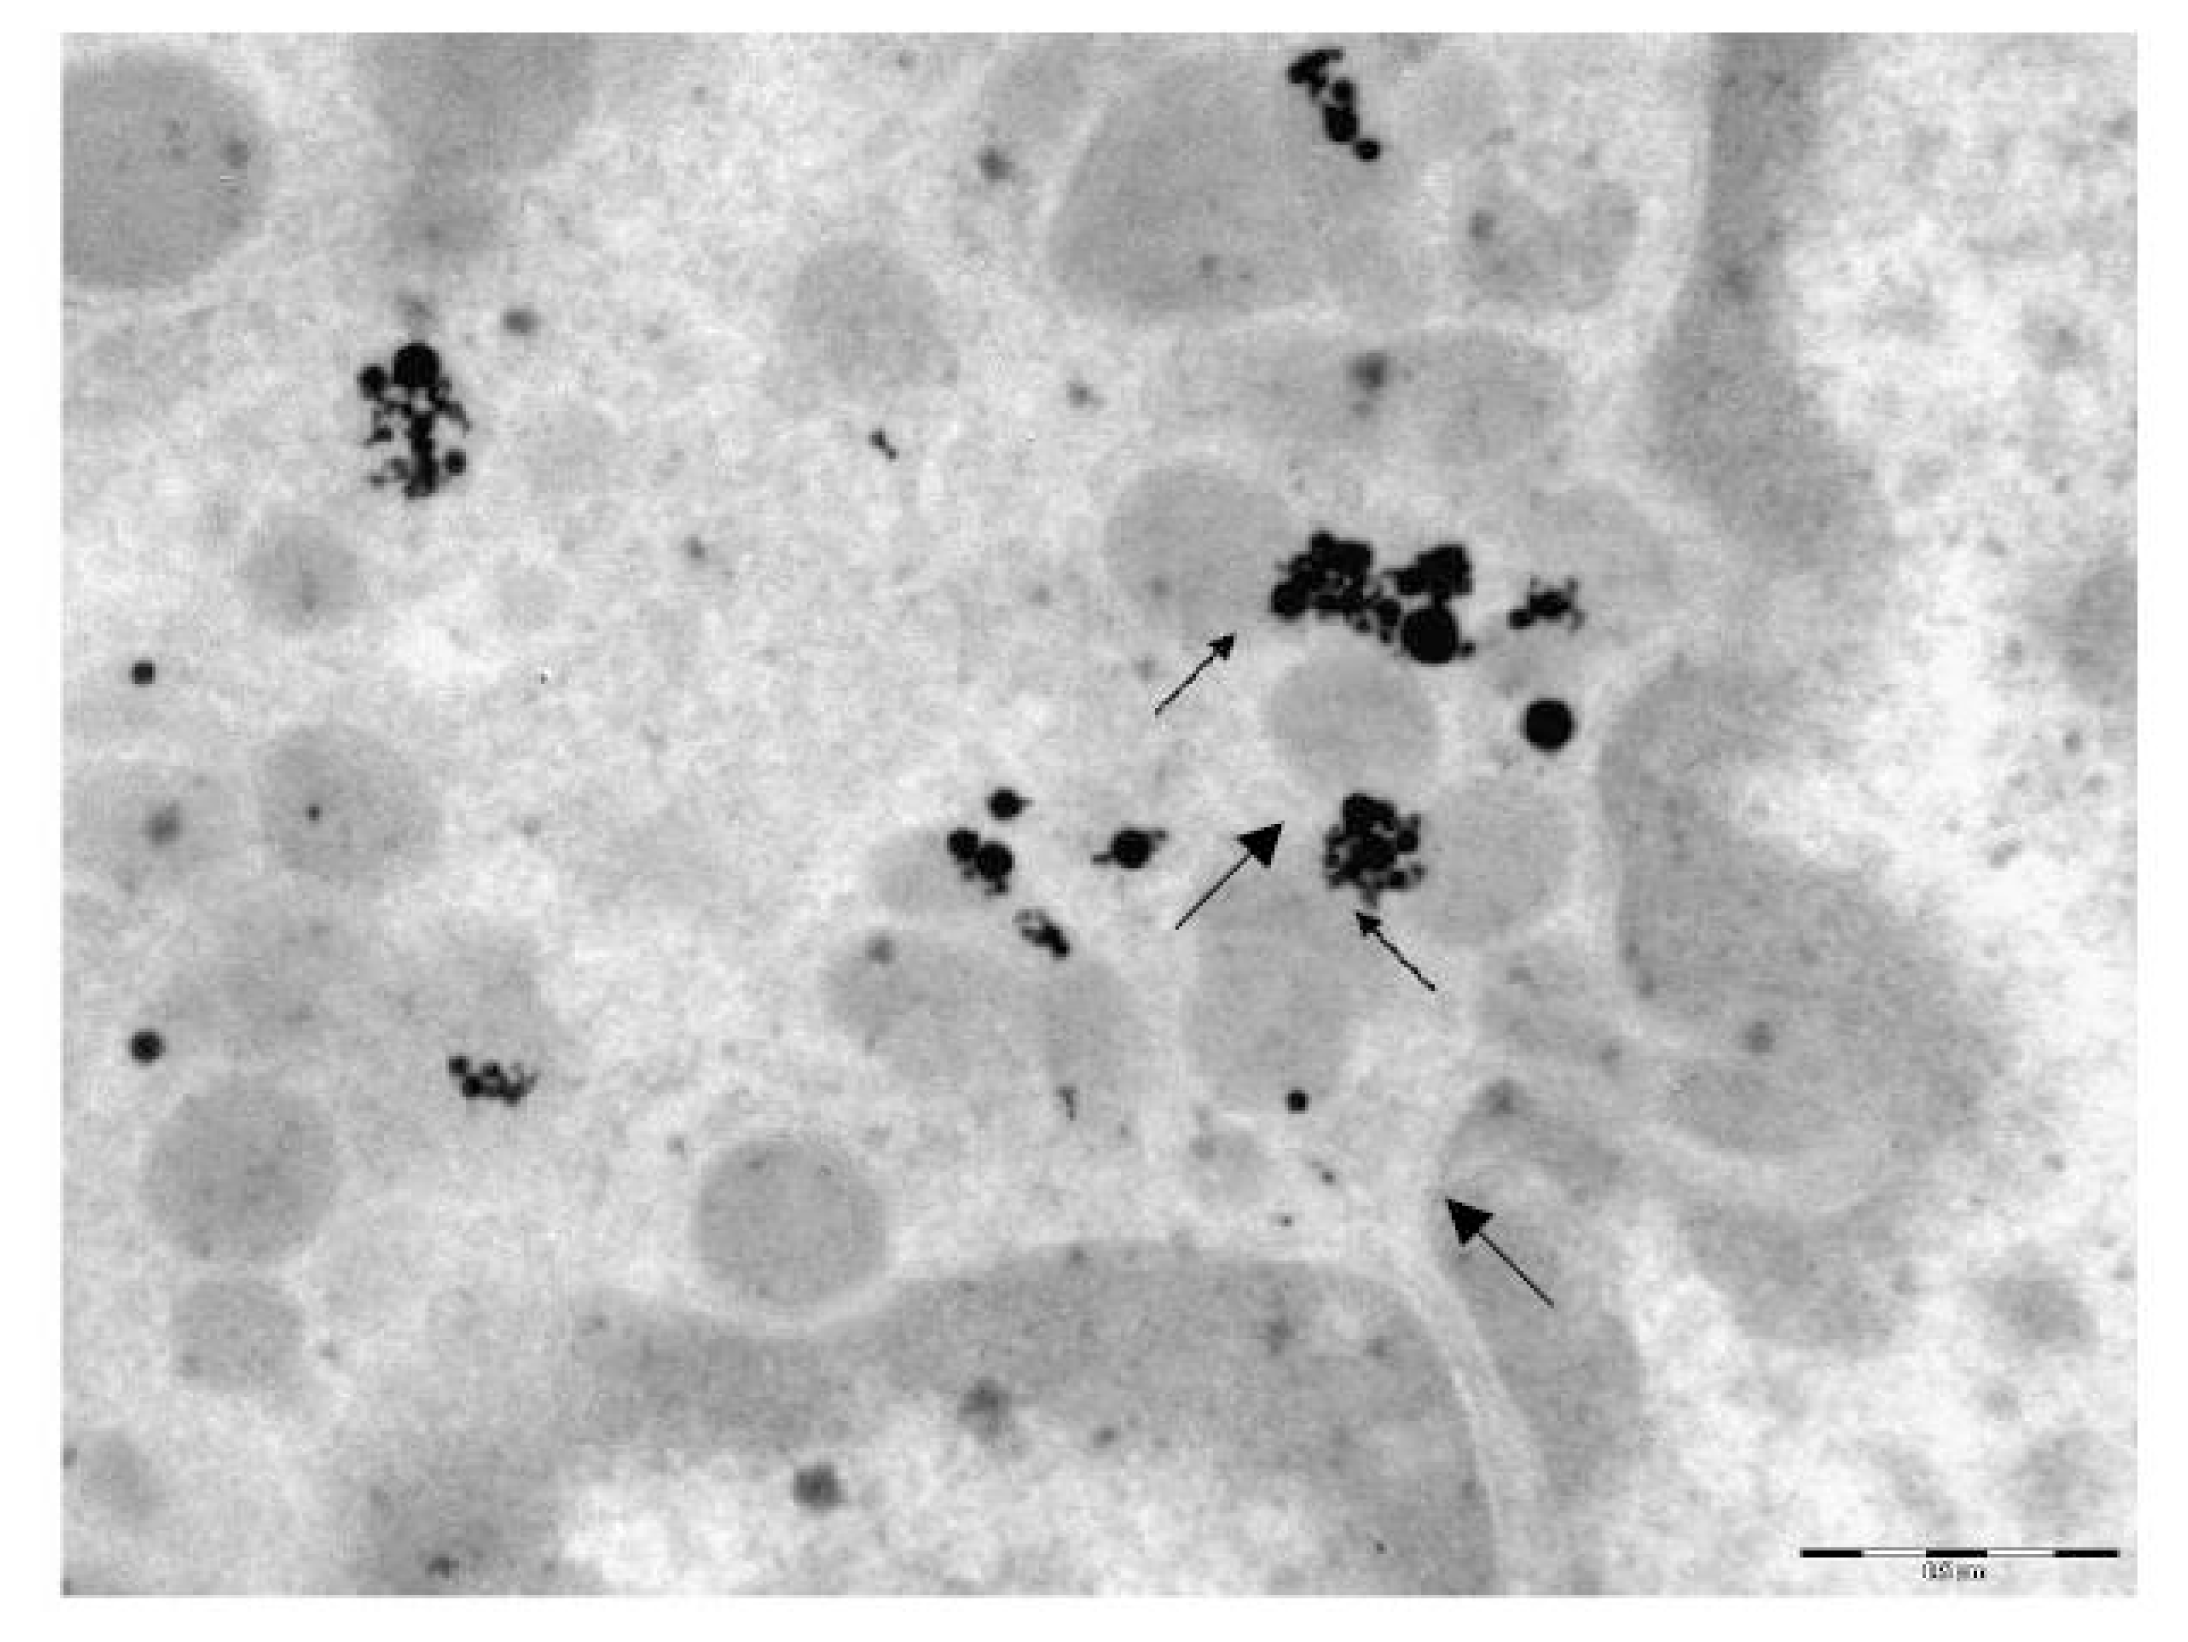

2.1.3. Transmission Electron Microscopy (TEM) Data

Nanosilver. Silver nanoparticles are not found in every cell—where they do occur, their quantities range from solitary NPs or moderate numbers, to considerable amounts. Unlike NG, NS is not found near the plasma membrane, either inside or outside the cells. They are mainly localized in deep regions of the cytoplasm, probably having had migrated there over the time interval from the moment of their in vivo contact with the cell to the moment of its drying. Comparison with the above-described picture of intracellular NG particle distribution suggests that NS particles migrate faster. Nevertheless, in one of the TEM pictures, we did discover a two-particle aggregate that had just penetrated through the plasma membrane with the formation of a phagosome. Phagosomes located deeper in the cell contain both single particles and their aggregates. However, it is impossible to judge whether the latter had penetrated into the cells in preformed state or had formed inside merged phagosomes. (The second mechanism seemed more likely for 10 nm particles of iron oxide, judging by the pattern of their distribution inside AM [4,5]).

Particle aggregates are most often localized inside mitochondria either on the cristae or on the inner surfaces of their membranes (Figure 4 and Figure 5). In some mitochondria, these aggregates are so large that they occupy almost the entire organelle, but sometimes single NPs are also found inside the mitochondria. Both mitochondria that closely interact with particles and those that are free from direct contact with them demonstrate signs of destruction: only part of the cristae is intact, or just their fragments are visible; homogenization of the mitochondrial matrix is observed; the two-contour membrane is fragmented or is not found at all. Lysosomes are observable in the cytoplasm in approximately the same quantity as in the control preparations.

No silver NPs have been revealed inside the nucleus in any of the cells examined. In just one case, there is a large aggregate of particles in a phagosome near the nucleus, and in another TEM image a single NP is observed getting through the nuclear membrane without breaking the latter. Singlets are also observable near the nucleus without direct contact with it, and, in such cases, changes in the nuclear membrane are non-uniform. It may be blurred, and its two-contour organization damaged near a large singlet, but, at the same time, the nuclear membrane near a small aggregate consisting of medium-sized particles may be distinct, with a clearly visible two-contour organization.

Similar to NG, no difference between AM and NL as concerns the localization of internalized NS particles has been revealed.

Thus, the principal distinctions in the electron-microscopy images of pulmonary phagocytes exposed to NG and NS particles may be summarized as follows:

• NG particles are observed mostly as singlets and are fairly uniformly distributed, while NS particles tend to form aggregates

• Unlike NG particles, NS ones are virtually absent in the cell nuclei.

• NS particles tend to show greater tropism towards mitochondria than NG ones, accumulating in greater quantities within them and causing more marked destruction of the membranes and cristae.